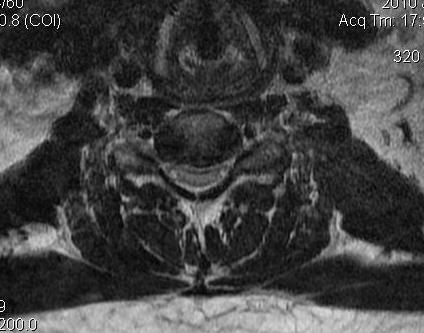

2. Compression Ratio

- banana cord

- divide the smallest AP diameter by largest transverse diameter at same level of spinal cord

- ratio of < 0.4 after decompression particularly with myelopathy > 6 months has poor prognosis

Banana shaped cord